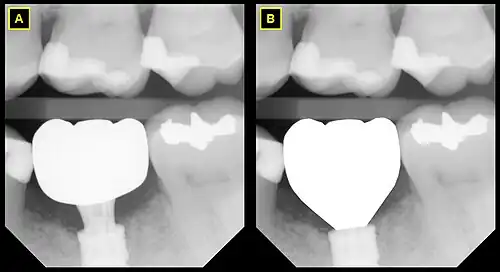

B This emergence profile respects the gingival architecture and emerges fully subgingivally.

In implant dentistry, running room refers to the apico-coronal distance between the platform of a dental implant and the gingival margin. It is a critical factor in restorative implant dentistry because it is effectively the "vertical distance [available subgingivaly] to make a transition from the smaller diameter prosthetic platform of an implant to the larger cross-sectional cervical shape of the tooth being restored."[1] The term was coined by Jonathan Zamzok, a Manhattan prosthodontist, in the late 1990s.[2]

Adequate running room is necessary to allow the implant-supported crown to exhibit a tooth-shaped contour despite the smaller diameter and circular nature of implant platforms.[3] For example, the mean mesial-distal dimension of a maxillary central incisor at the points at which it contacts the adjacent teeth is 8.6 mm, and the mean mesial-distal dimension of the same tooth at the cementoenamel junction (CEJ) is 6.4 mm.[4] Even though the implant diameter chosen for the maxillary central incisor is usually around 4–5 mm, the supragingival tooth contours need to mimic those of the natural tooth if esthetic success is intended.

As the anatomical crown and root tapers towards the apex, the mesial-distal dimension decreases, and so the mean mesial-distal dimension at the marginal crest of bone, which lies approximately 2 mm apical to the CEJ, is smaller. The tooth has the apico-coronal distance from the marginal crest of bone to the contact point in order to increase from the much narrower mesial-distal dimension to the greater mesial-distal dimension, and this distance is subgingival (below the gum line). Running room refers to this subgingival apico-coronal distance.

In general, it is recommended that implants be given approximately 3mm of running room in compliance with the rule of thumb that implants should be placed as deep as necessary and as shallow as possible.[5]